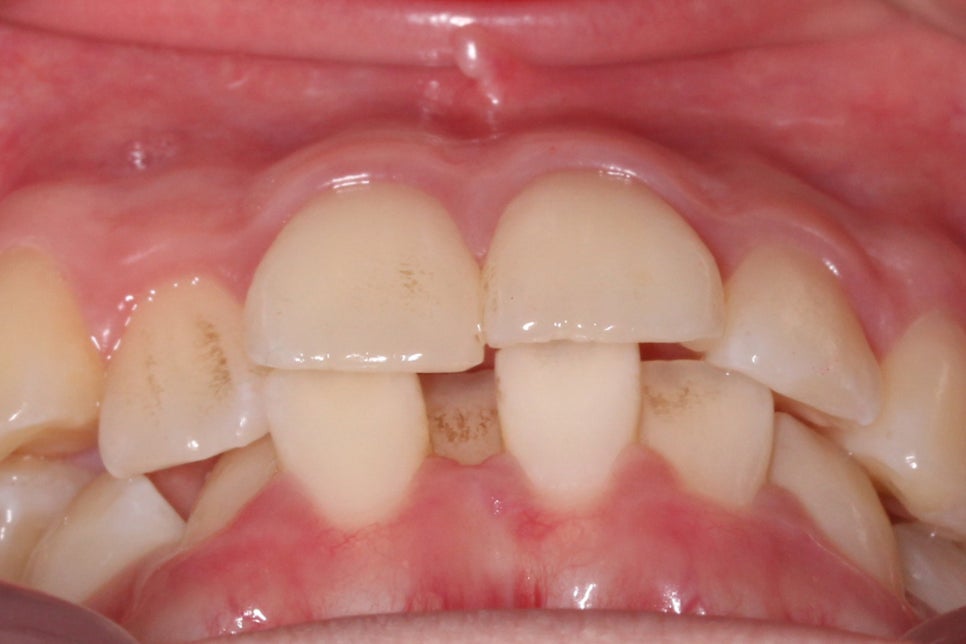

다음으로 overbite 사진입니다.

전치부가 교합된 모습을 보면

상악에 비해 하악의 crowding이

심한 모습을 확인할 수 있는데요,

아랫니가 배열된 각도가 앞뒤로 심하게

삐뚤거리는 모습으로 이러한 경우

삐뚤어진 치아 사이 사이로

음식물이 쉽게 쌓이게 되고

치아를 관리하기가 어려워

치석이 발생할 수 있습니다.